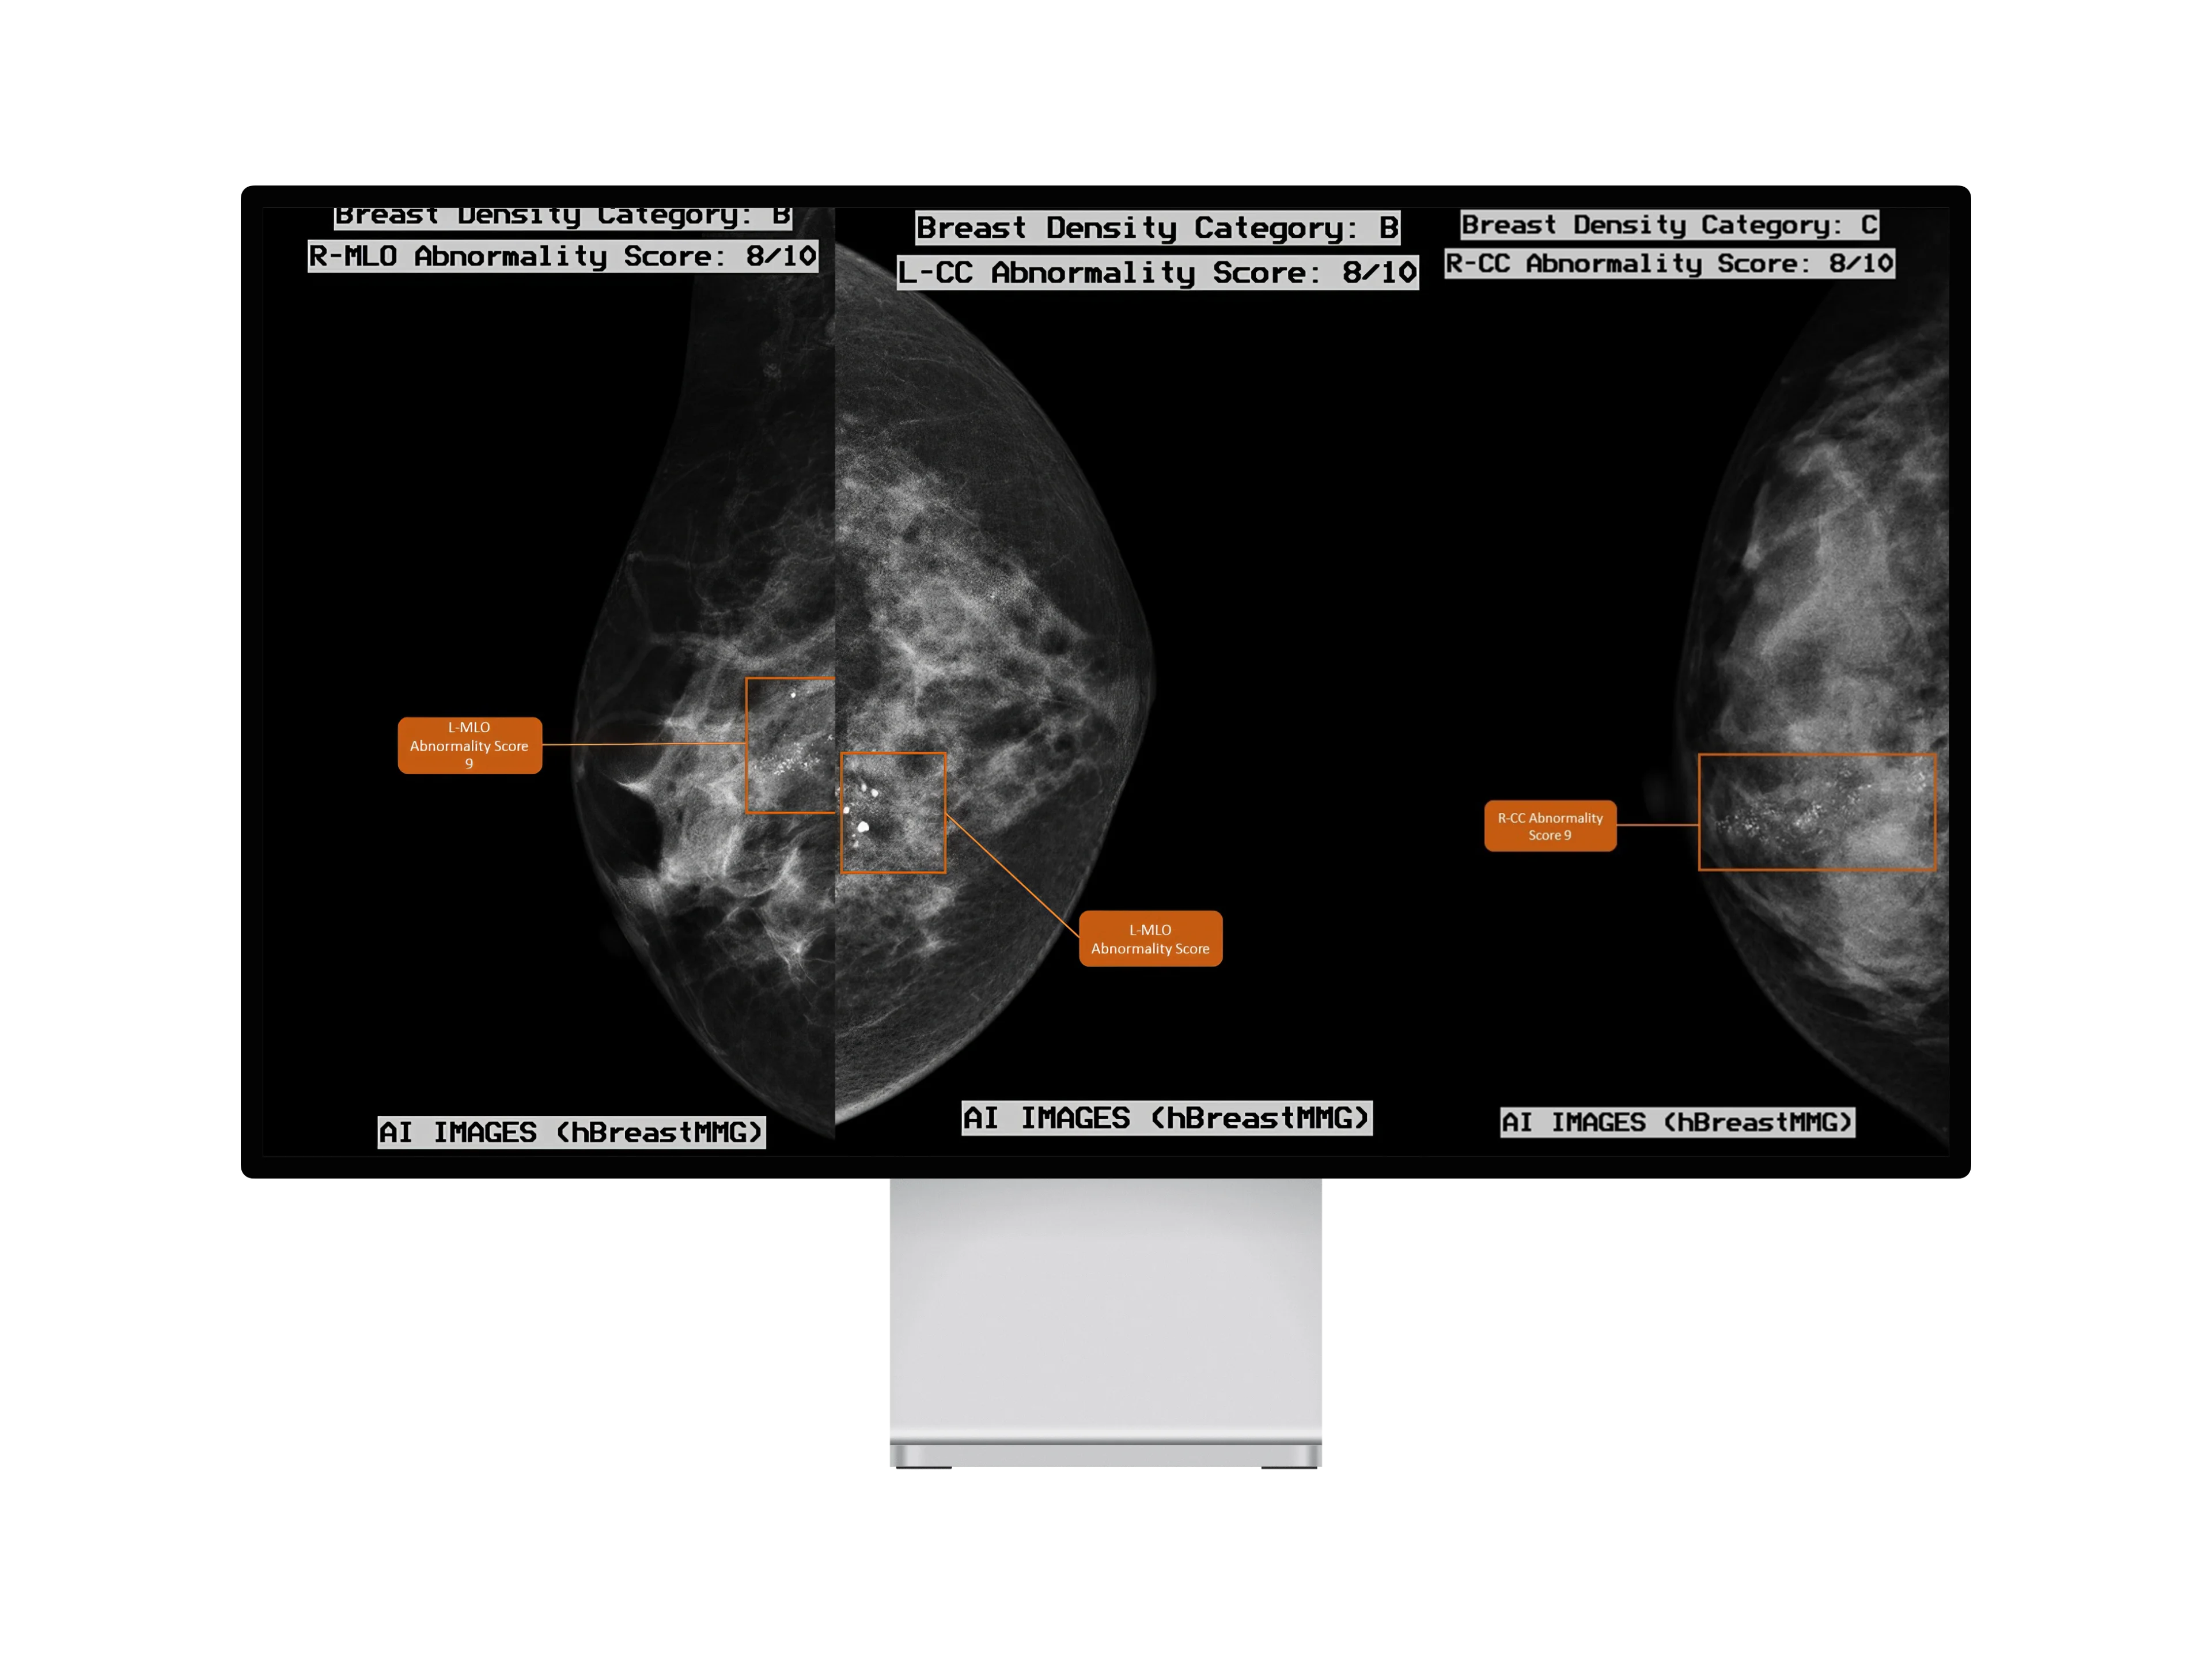

hBreastMMG

Empowering mammogram interpretations with AI-driven precision, hBreastMMG transforms breast cancer diagnostics.

Advanced Breast Density Assessment:

Utilizing the ACR-BIRADS 2013 guide, hBreastMMG offers accurate breast density categorization, facilitating more informed diagnostics.

Elevated Diagnostic Confidence:

By evaluating lesions and calculating their potential indication of breast cancer, combined with AI-powered confidence scores, hBreastMMG ensures radiologists are equipped with precise insights.

hBreastMMG Key Features Include:

• Harnesses state-of-the-art deep learning technology for meticulous mammogram analysis.

• Breast density assessment (categories A, B, C, and D) as per the ACR-BIRADS 2013 guide.

• Determination of BIRADS scores for precise mammographic interpretation.

• Evaluation of lesions and calculation of their probability of being indicative of breast cancer.

• AI-powered confidence scores to augment diagnostic precision.

• Visual representation of BIRADS scores and breast density categories for enhanced clarity.